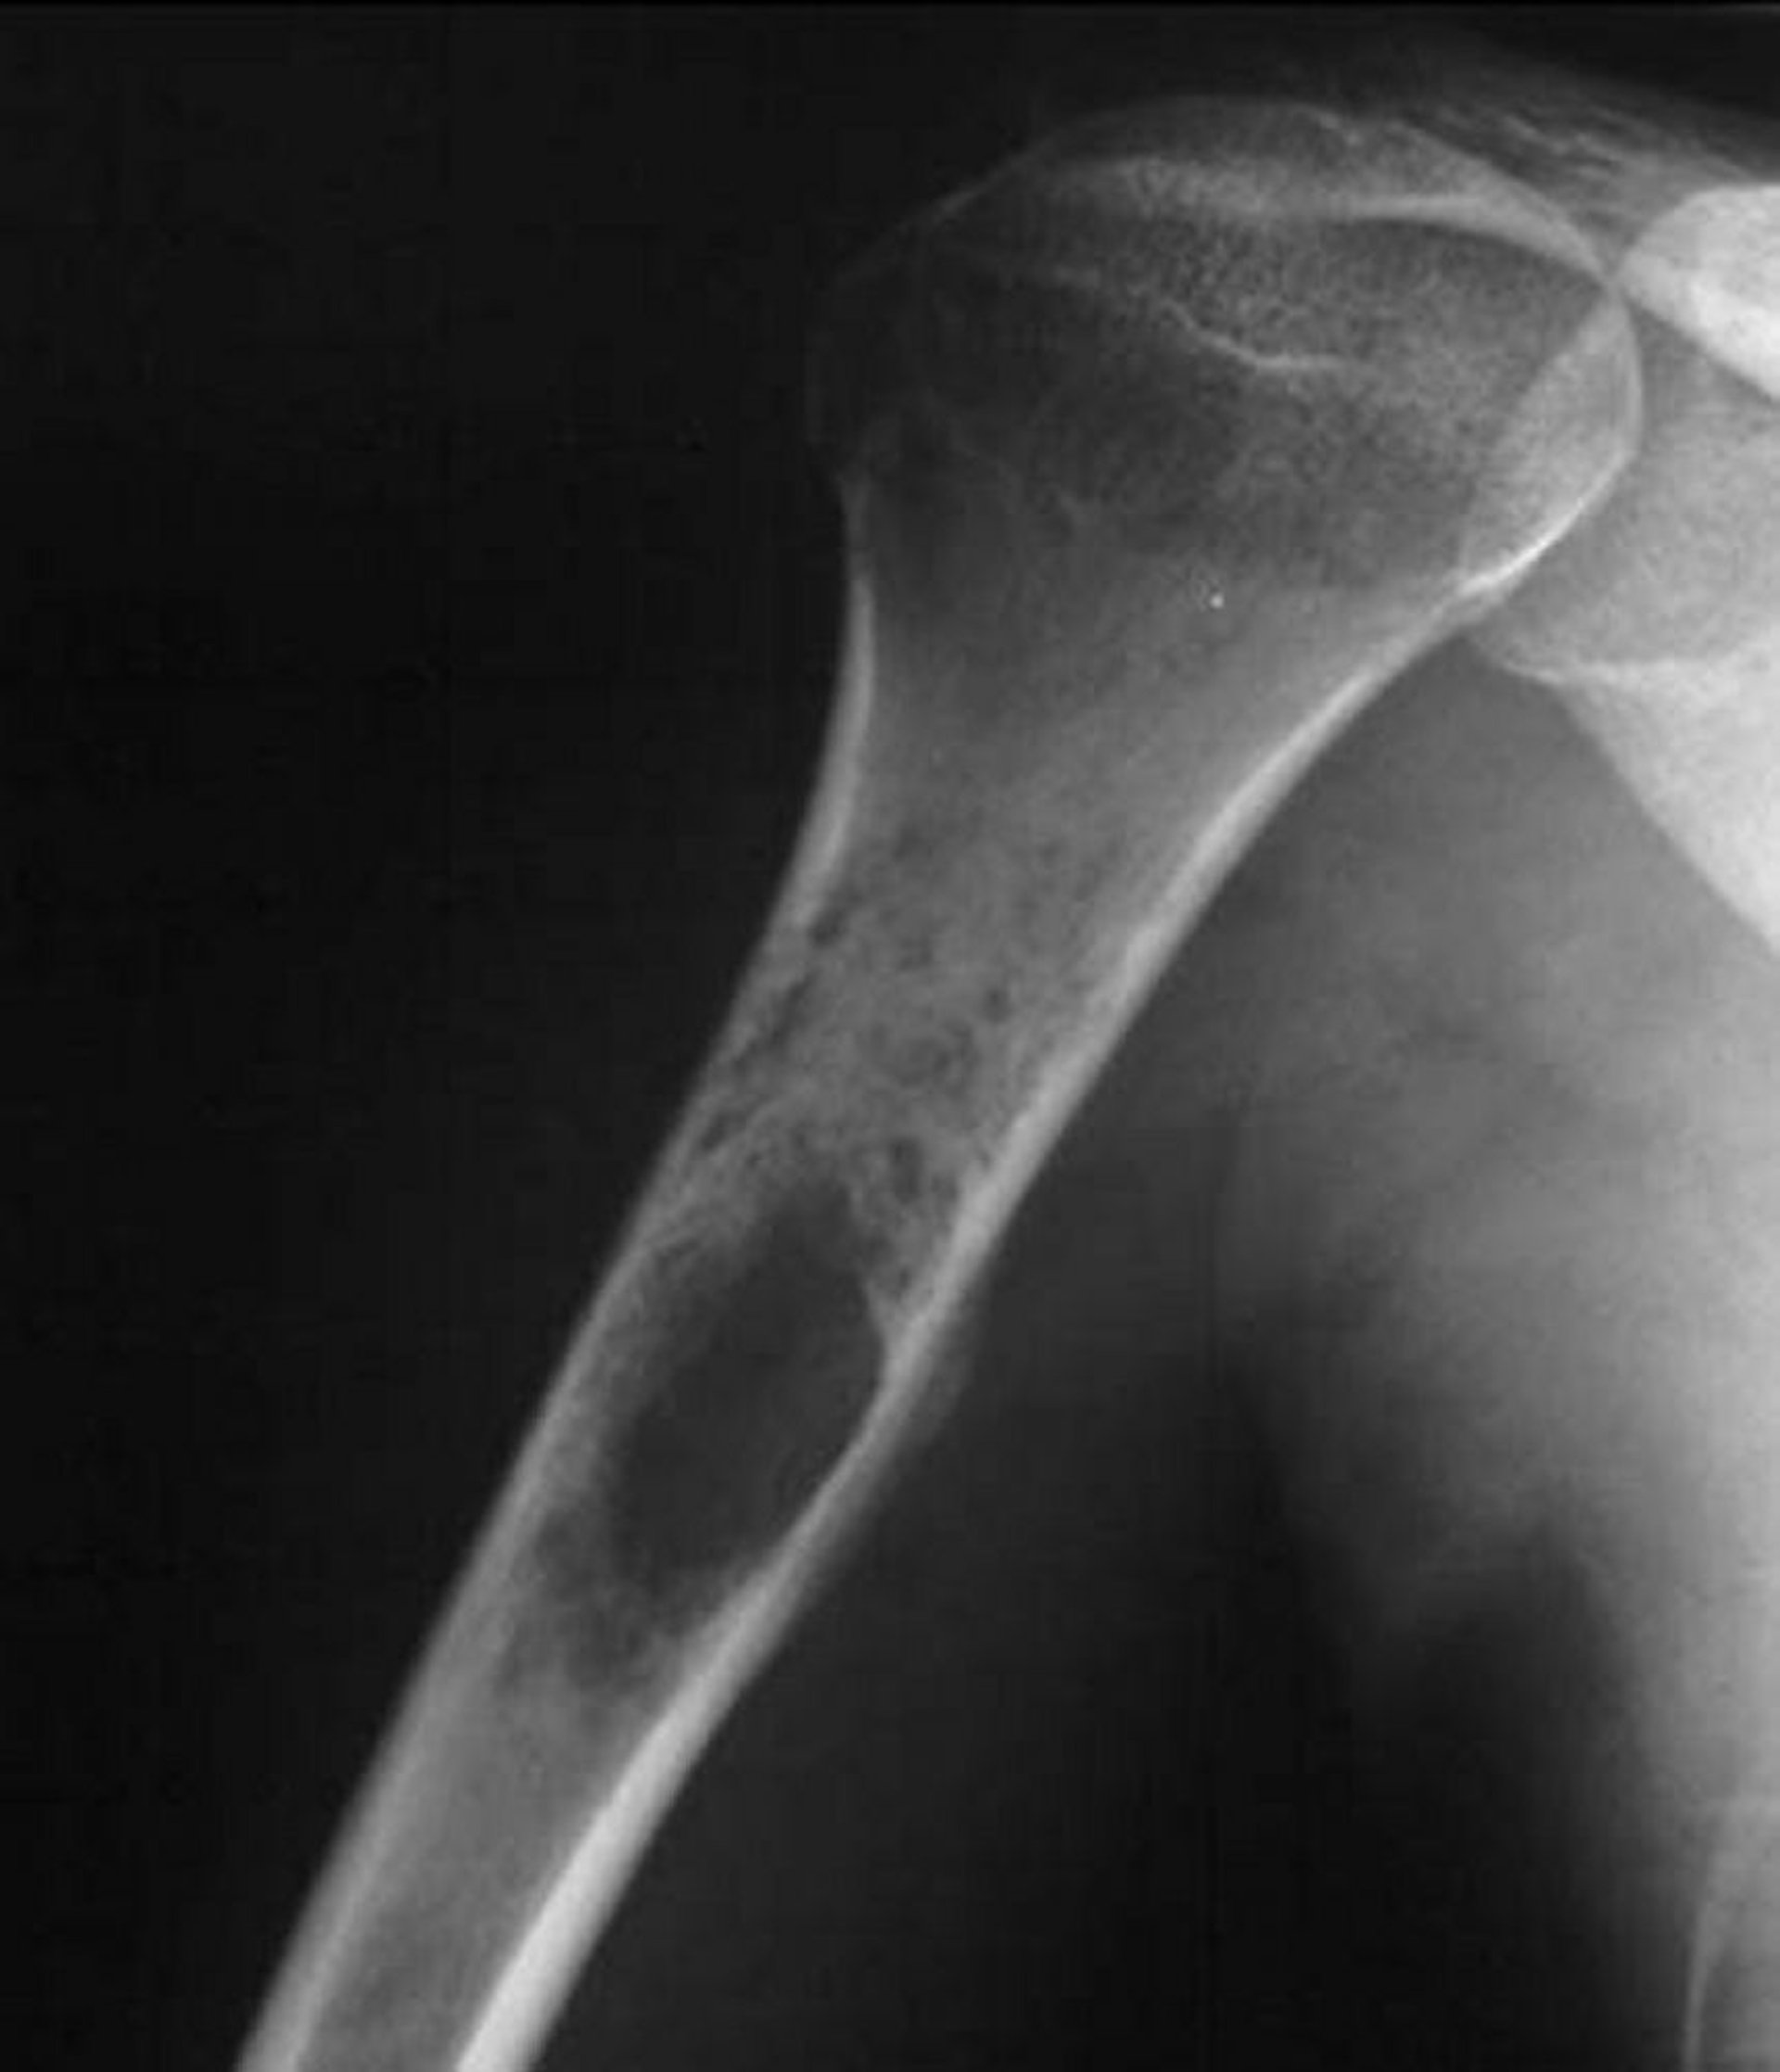

Ewing-Sarkom des Knochens

Diese Röntgenaufnahme der Schulter zeigt einen permeativen destruktiven Tumor, der im proximalen Humerus entsteht, der typisch für das Ewing-Sarkom ist.

Image courtesy of Michael J. Joyce, MD, and Hakan Ilaslan, MD.